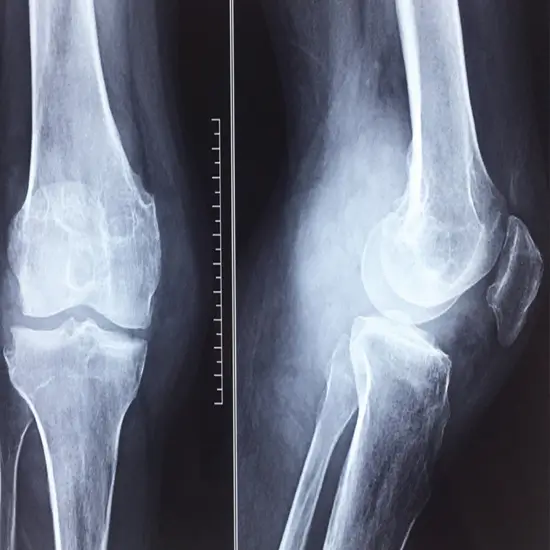

CECT Right Knee Joint or Contrast Enhanced Computed Tomography for the Right Knee Joint is an imaging scan to view the right knee joint and its surrounding tissues. This scan uses a computer, an X-ray beam, and contrast media to obtain a clear picture of the right knee joint.

A CT scan helps in the production of high-resolution scan images of the knee region. The scan images are created using the radiation principle to help in the detection of abscesses, infections, or broken bones of the knee joint.

A CECT knee joint scan can provide more details and in-depth representation of the joint and surrounding hard and soft tissues structures. The soft tissues that are visualised in the scan images are tendons, muscles, ligaments, and other tissues, thereby helping in the diagnosis of torn ligaments.